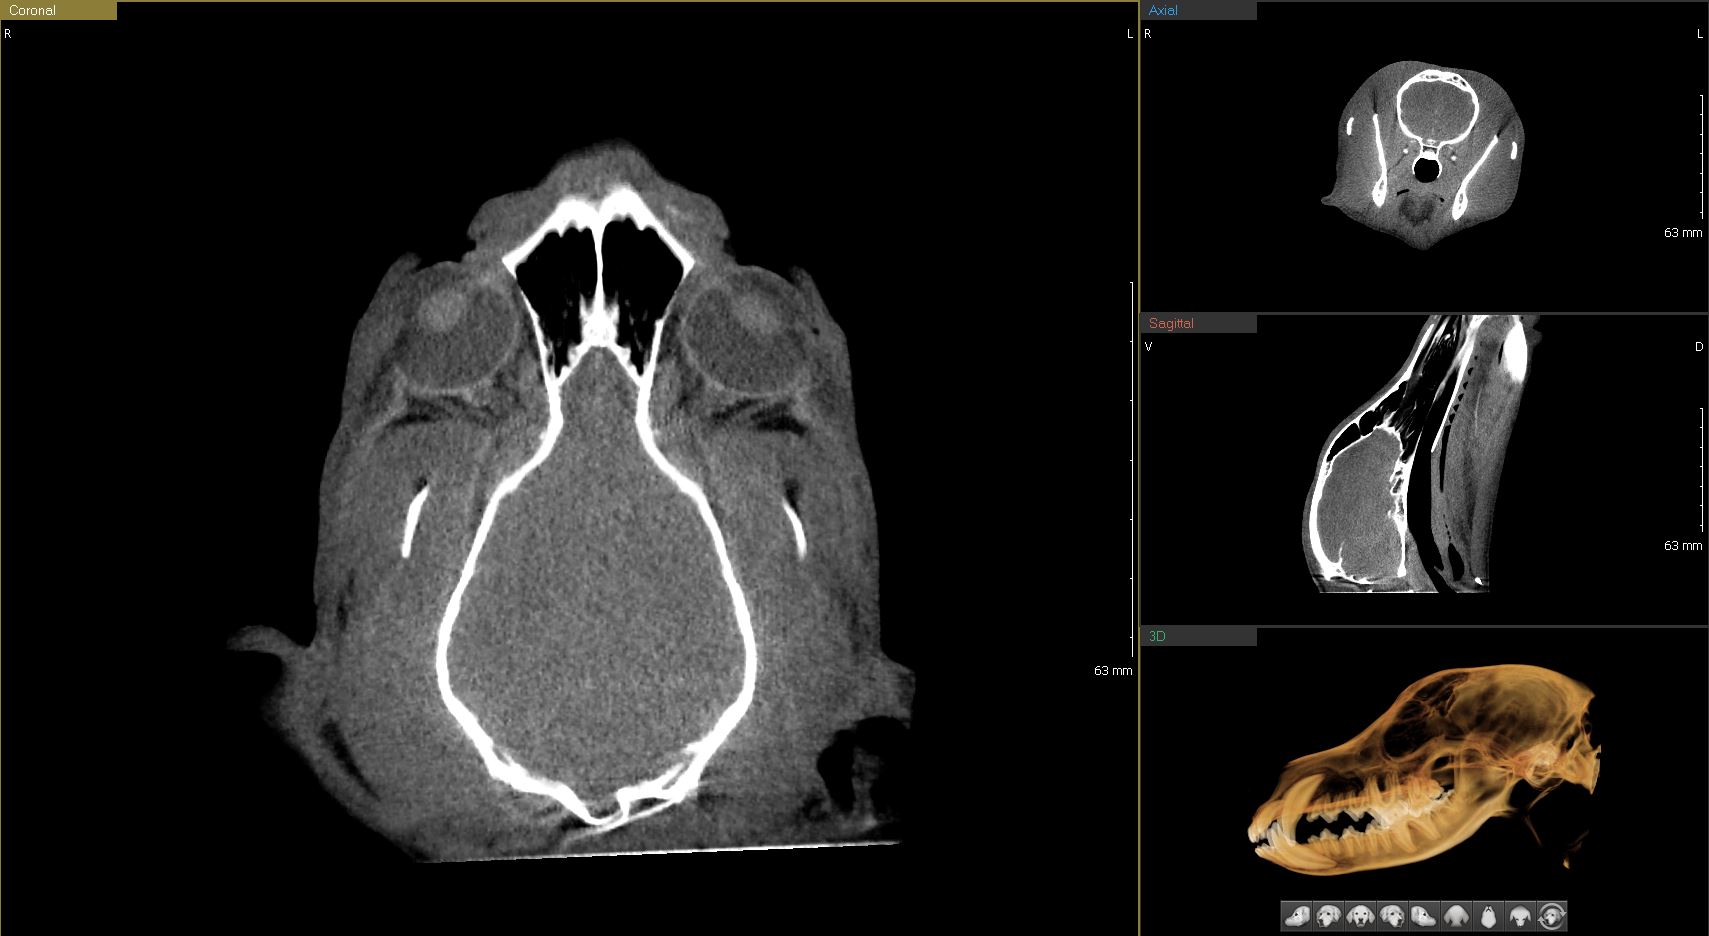

연산동물의료센터의 CT검사는 짧은 촬영으로도

정밀한 3D 입체영상을 얻을 수 있습니다.

강아지 코 이미지

Woorien Veterinary CT

“15분에서 30분 정도의 빠른 촬영 시간으로 마취 부담 최소화”

수의학에 최적화된 동물전용 CT

반려동물의 안전을 생각한 선량 CT

인체 CT보다 빠르게 촬영 & 영상 확인 가능

내과, 정형외과, 치과, 안과, 이비인후과까지 다양한 영역 진단 가능

두부비강, 안구, 구강, 두개골 및 뇌 내 실질